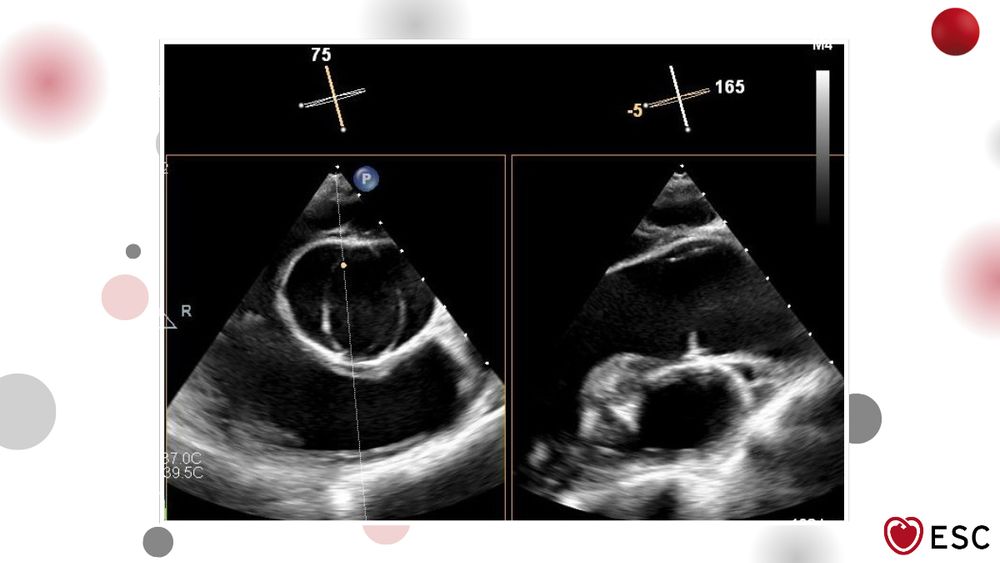

#ImageOfTheWeek by Anish Adhikari and Caleb Wutawunashe from Lenox Hill Hospital, New York, New York, USA.

What aortic valve abnormality is shown on TEE? ow.ly/2tAt50X4WJg